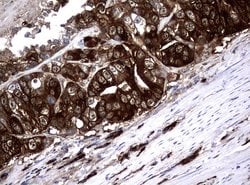

NME1 Mouse anti-Canine, Human, Rat, Clone: UMAB94, liquid, UltraMAB™

NME1 was identified because of its reduced mRNA transcript levels in highly metastatic cells. Nucleoside diphosphate kinase (NDK) exists as a hexamer composed of ′A′ (encoded by this gene) and ′B′ (encoded by NME2) isoforms. Mutations in the gene have been identified in aggressive neuroblastomas. Two transcript variants encoding different isoforms have been found for this gene. Co-transcription of this gene and the neighboring downstream gene (NME2) generates naturally-occurring transcripts (NME1-NME2), which encodes a fusion protein comprised of sequence sharing identity with each individual gene product.Specifications

| Immunocytochemistry, Immunofluorescence, Immunohistochemistry (Paraffin) | |